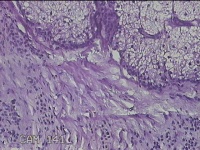

左面部赘生物

性别

男

年龄

47岁

临床诊断

纤维瘤;皮肤感染

一般病史

面部皮肤起赘生物8年。

标本名称

大体所见

灰白粉红色肿物1.3x1.2x0.3cm一个,表面光滑,肿物表面有少许毛发,切面灰白粉红色,质软。

图1